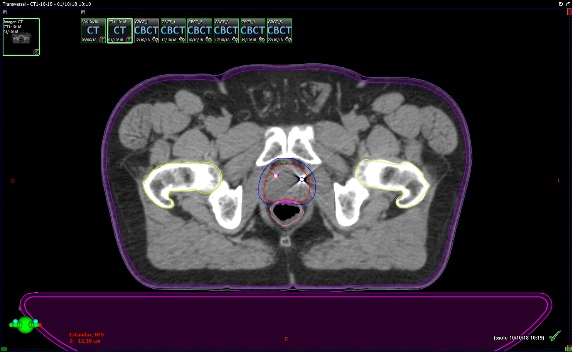

Fig. 3. Técnica de Radioterapia IGRT (Guiada por imágenes). Derecha: TAC de simulación con contornos: Rojo CTV: clinic target volume(próstata y vesículas seminales); Azul: PTV: patologic target volume); Amarillo: Vejiga (OAR); Rosado: Recto (OAR); Verde: Cadera derecha (OAR); Celeste: Cadera izquierda (OAR). Izquierda: Conbeam en máquina de tratamiento, en donde la imagen en el aceleradorse superpone con los contornos hecho en el TAC de simulación.